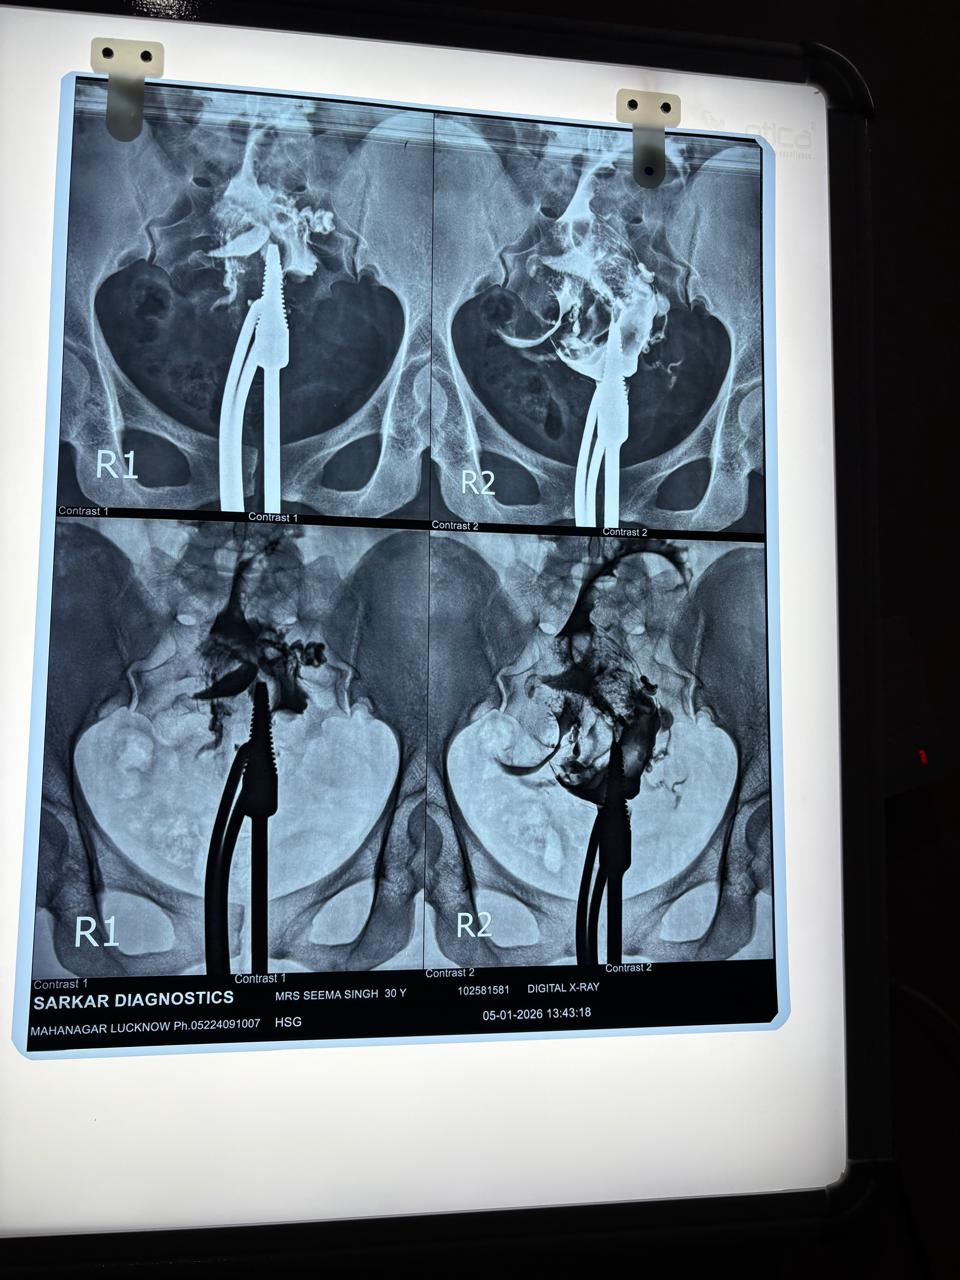

Mrs. Seema presented to our facility on May 23, 2025, diagnosed with a right tubal ectopic pregnancy—a condition that poses serious risks of rupture and internal hemorrhage if not treated immediately. Our gynecological surgical team conducted a thorough evaluation and proceeded with a specialized Laparotomy with Salpingotomy While the priority was the patient's immediate safety, our surgical approach was meticulously planned to protect her future reproductive health. The surgery was performed without complications. However, the true success of this case was confirmed during the 3-month follow-up. A Hysterosalpingography (HSG) test revealed an excellent outcome: the fallopian tubes were confirmed to be patent (open). This crucial diagnostic result means the patient has successfully retained her potential for natural conception. She is now medically cleared and prepared for future pregnancy planning, turning a medical emergency into a story of hope.

Visual Documentation

Clinical Outcome

Full recovery with confirmed tubal patency (HSG), clearing the path for future pregnancy planning.